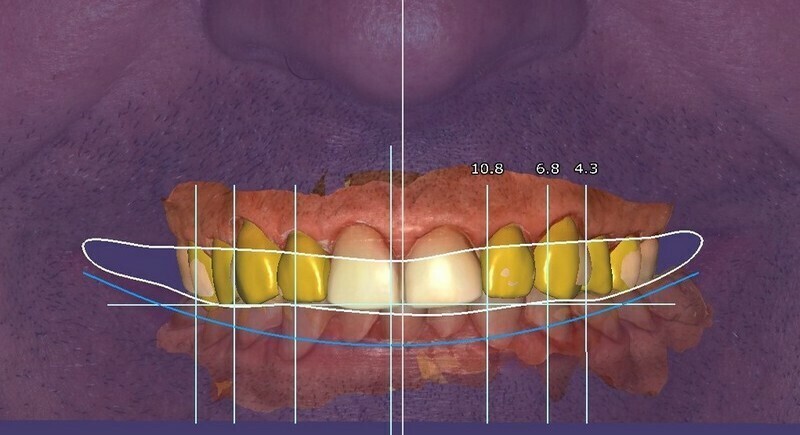

Des images photographiques en 2D et des images en 3D ont été couplées pour concevoir la réhabilitation du sourire et la proposer au patient.

L’occlusion (rencontre des dents) est optimisée.

A l’aide d’un jeu de maquettes et d’usinage, les restaurations respectent le projet initial.